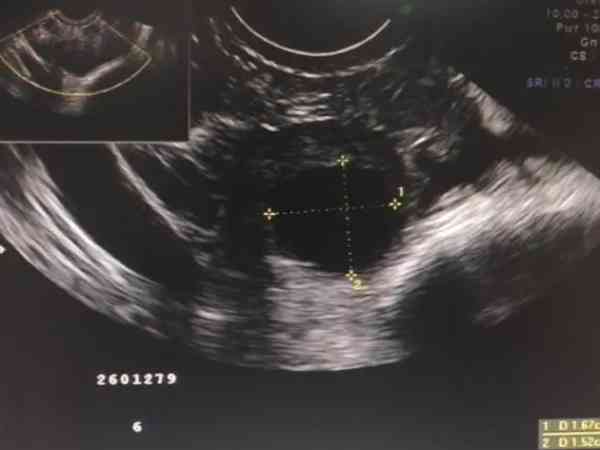

女性在排卵期同房受孕機率比平時更大,因此尋找合適的時機是很重要的,判斷排卵期的方法比較多,在醫院監測卵泡發育情況是最準確的一種,由於這種方法需要做B超,為了保證結果的準確性,很多女性都想知道在什麼時間段去做檢查是最合適的。女性要到醫院做B超監測卵泡發育情況的話,選擇時間很重要,婦科醫生認為在上午和下午都是可以的,卵泡監測對於檢查時間沒有要求,只需要記住監測日期即可,尤其是在卵泡發育快成熟的時候,此時隨時可能排卵,除了監測之外,還可以適時安排同房。

做卵泡監測就是去醫院做彩超檢查,上午或下午應該都是可以的,時間對於監測結果並沒有什麼影響,畢竟它是觀察卵泡的影象,B超什麼時候做影象受到的影響都不大,所以說上午或者下午做檢查都是可以的。

卵泡的發育情況與早上還是下午沒有太大的關係,上午測到的卵泡在下午可能會長,不過這種變化並不大,因為卵泡越臨近成熟時發育速度就越慢,所以說上午和下午監測卵泡的變化並不大。

一般卵泡在24小時之內才可以長0.1釐米的,而上午和下午監測卵泡間隔時間並不久,因此大多數情況下測出來的結果是一樣的,有需要監測卵泡的女性可以根據自身情況選擇何時去做檢查。